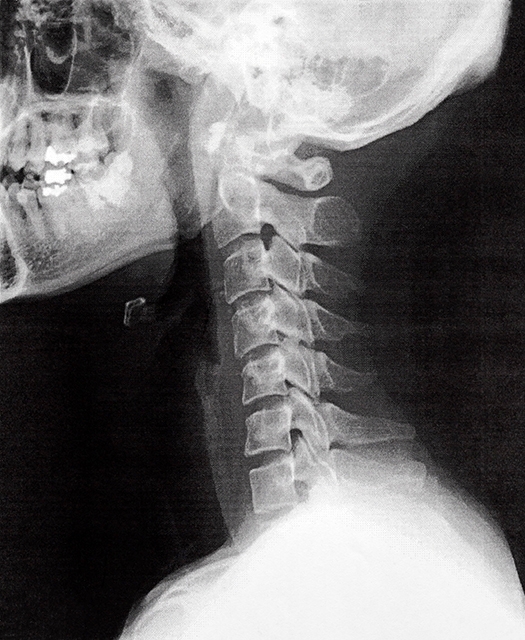

肩こりや手のしびれは「首」が原因かも

肩や腕、手先のしびれや重だるさは、単なる肩こりではなく、首から伸びる神経の影響で起きていることがあります。首から肩・腕・手に向かう神経は、筋肉や筋膜に囲まれながら通っており、ここで圧迫されたり、滑らかに動かない状態「滑走障害」が起こると、手先まで症状が現れることがあります。

首の神経根が圧迫されることで直接神経が影響を受けるタイプ

首をゆっくり後ろに倒してみて、肩や腕、手の先までジーンとしびれや違和感が広がる場合、首の神経根(神経の出口)が圧迫されている可能性があります。特に、しびれの範囲と首の動きが連動して悪化する場合は、首由来のしびれである可能性が高いです。